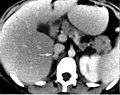

Pheochromocytoma. CT abdomen.

Imaging by computed tomography or a T2 weighted MRI of the head, neck, and chest, and abdomen can help localize the tumor. Tumors can also be located using an MIBG scan, which is scintigraphy using iodine-123-marked metaiodobenzylguanidine. Even finer localization can be obtained in certain PET scan centers using PET-CT or PET-MRI with [18F] fluorodopamine[8] or FDOPA.[9]